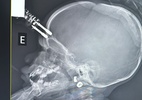

Uma bebê de um ano e quatro meses passou por cirurgia de urgência após cair da cama, em Divinópolis (MG), com um carregador de celular cravado na testa, que atravessou o crânio e atingiu o cérebro. Apesar do susto, a menina já se recupera em casa.